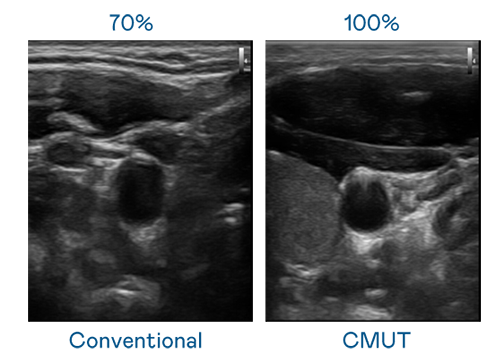

CMUT 技术是一种用电容式微机电元件来产生超音波讯号的技术。与传统 PZT 压电式技术相比,CMUT 频宽增加 30%,更宽频的超音波讯号让影像解析度大幅提升,是实现高影像品质医疗超音波扫描、促进精准医疗发展的关键技术。

大频宽带来超清晰影像

超音波影像的解析度高低,首先取决于探头能发出的讯号频宽。永乐高 CMUT 可提供高清晰的超音波讯号,提供高频宽、高灵敏度、影像纹理细节更高的超音波影像,协助医护人员缩短影像判读时间及利用精准的医疗影像进行诊断。